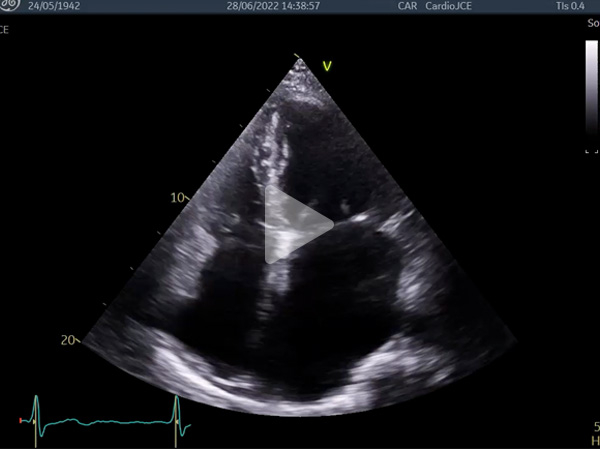

Vidéo 1 : HVG concentrique, petite cavité VG, dilatation biatriale sévère

- Phénotype typique : petite cavité VG, hypertrophie modérée, dilatation OG sévère, profil mitral, VCI dilatée